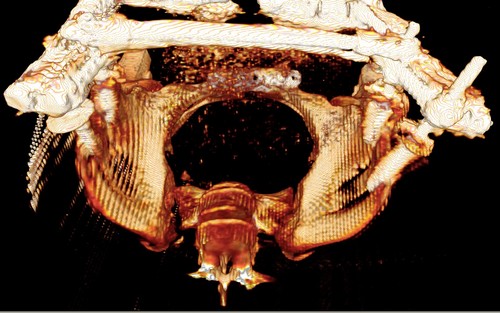

Девочка 14 лет. Кататравма (падение с высоты 4-5 этажа). Вертикально нестабильный перелом таза со смещением, разрывом лонного и левого подвздошно-крестцового сочленения, перелом крестца, открытый перелом костей голени. Ребёнок оперирован на 10-е сутки после травмы - выполнили максимально возможную репозицию на ортопедическом столе, синтез лонного сочленения реконструктивной пластиной (из имеющихся пластин - на 7 дыр - самая длинная, получилось только по 2 шурупа с каждой стороны, поэтому пришлось подстраховаться проволокой), АВФ. Задний комплекс не фиксировали ввиду отсутствия канюлированных (да и неканюлированных)шурупов должной длинны.В настоящий момент перед нами стоит вопросов:1. Обязательно ли фиксировать подвздошно-крестцовое сочленение, либо фиксации АВФ будет достаточно? Аппарат стоит достаточно стабильно, девочка при перемещениях в пределах постельного режима болевых ощущений не испытывает.2. Что делать с отломком крестца, который довольно значительно смещён кпереди? В настоящий момент никаких проблем с дефекацией у больной нет, хотя, глядя на КТ, создаётся впечатление, что отломок прямо-таки лежит на прямой кишке. Репонировать-фиксировать? Просто удалить? Вообще не трогать? Не создаст ли он в дальнейшем проблем во время родов?Хотелось бы знать мнение уважаемых коллег.Заранее спасибо.

Здравствуйте, Сергей! Нестабильный перелом типа С подлежит обязательной задней фиксации или илиосакральными винтами, или пластиной, или стяжкой (кто что лучше умеет и чем оснащен). Возможен циркулярный АВФ (Уральский НИИТО). В Вашем случае, при невозможности восстановления заднего комплекса,- постельный режим до 2-х месяцев. Учитывая недостаточную репозицию в крестцово-подвздошном сочленении в будущем девочка обречена на хронический болевой синдром. Может быть стоило выполнить репозицию отломков в аппарате, а вторым этапом делать погружной остеосинтез. Костный фрагмент, думаю, можно оставить. После такой травмы речь будет идти о кесаревом сечении, а не о родах естественным путем.

Это не частый случай в детской практике. Вы очень хорошо сопоставили и фиксировали переднее полукольцо. Крестцово-подвздошное осталось в приличном смещении. Прекрасно - что нет неврологической клиники. Сейчас больная лежит. Поэтому всё хорошо. Учитывая соотношение крестец-подвздошная кость - кажется, что первые же проблемы возникнут при попытке поставить больного на ноги. Разорваны важнейшие стабилизирующие и воспринимающие нагрузку связки в системе позвоночник-крестец-таз. В таком положении фрагменов их адекватное восстановление и последующее функционирование , как мне кажется, не возможно. В возрасте 14 лет это взаимоотношение критично. Я имею в виду отсутствие репозиции. появление нестабильности, по-видимому, будет неизбежно. Это моё маленькое скромное мнение. Всё же надо было начинать сзади. Именно с репозиции. Фиксацию, ИМХО, можно было бы на безрыбье временно сделать и спицами (например-с резьбой) интраоперационно. В идеале - с навигатором, чтобы не задеть крестцовый канал, или с пальцем, контролирующим положение отломков над гребнем подвздоной кости и "навигирующим" проведение спицы. Сейчас Вам это сделать помешает LCP, жёстко фиксирующая переднее полукольцо и смещенное положение отломков. АВФ не "прижмёт" подвздошную кость к крестцу, и не выполнит репозицию. Возраст больной, мне кажется, не простит в дальнейшем погрешность в положении костей и, чем дальше, тем труднее будет исправлять . Это только мнение и ничего личного.Прямая кишка здесь в меньшей степени заинтересована - это вовсем не главное. Вероятные роды в насоящей тактике лечения совсем не играют решающей роли. Всё же - как неврология?